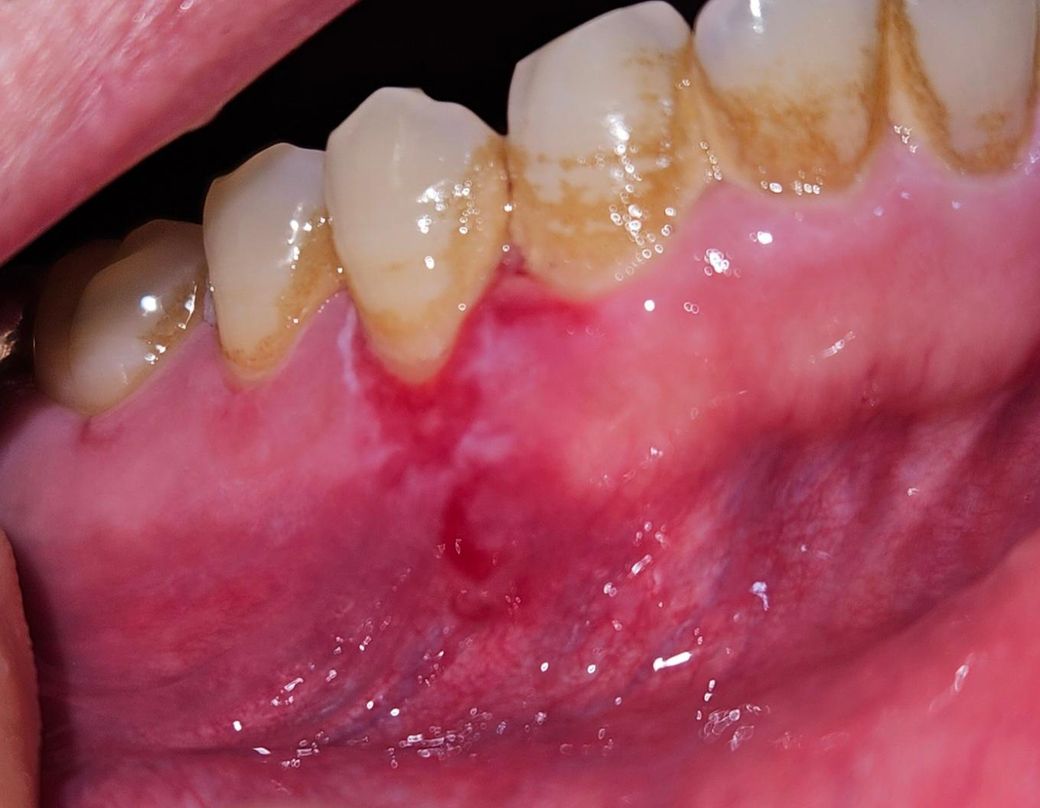

잇몸에 전반적으로 이러한 병변이 나타나고 있습니다

2개월정도 지속이 되고 있고 통증과 양치질할때 출혈이 나타나고 있습니다 치과에서는 면역력 문제라고 하는데 다른문제가 있는건 아닐까요?

• 3번 째 사진

구내염일수도 있지만 오랜기간동안 지속된다면 대학병원 구강내과를 가셔서 검진을 받아보시는게 좋을것같습니다.

면역질환이나 바이러스, 세균 감염 가능성을 먼저 따져봐야 합니다 지체하지말고 구강내과 가보시기 바랍니다